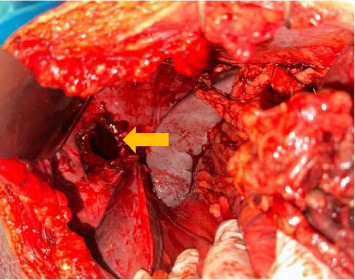

创伤后膈疝(PTDH)被定义为由创伤引起的膈病理缺损引起的腹内器官向胸腔内迁移。PTDH是一种罕见的疾病,发生在所有胸腹损伤的3%-7%。大约14.6%的PTDH病例在初次创伤后数月至数年出现。延迟PTDH并发肠梗阻和穿孔的病例极为罕见,据报道患病率为0.17%-6%。在非洲,在过去三十年中记录的延迟PTDH病例不到10例。尽管有已发表的报告,但目前尚无管理PTDH的既定实践指南。在这里,我们提出一个延迟PTDH的情况下,表现为急性肠梗阻12年后枪伤到胸部。这种情况导致了致命的术后结果。本病例强调了临床医生在有创伤史的急性肠梗阻患者中考虑PTDH的迫切需要,并强调了紧急手术治疗以防止致命并发症的重要性。

Post-traumatic diaphragmatic hernia (PTDH) is defined as the migration of intra-abdominal organs into the chest through a pathological defect in the diaphragm caused by trauma. PTDH is a rare condition, occurring in 3%-7% of all thoracoabdominal injuries. Approximately 14.6% of PTDH cases present months to years after the initial trauma. Cases of delayed PTDH complicated by bowel obstruction and perforation are exceedingly uncommon, with a reported prevalence of 0.17%-6%. In Africa, fewer than 10 cases of delayed PTDH have been documented over the past three decades. Despite the availability of published reports, there are no established practice guidelines for managing PTDH. Here, we present a case of delayed PTDH that manifested as acute bowel obstruction 12 years after a gunshot wound to the chest. The condition led to a fatal postoperative outcome. This case highlights the critical need for clinicians to consider PTDH in patients with a history of trauma presenting with acute bowel obstruction and underscores the importance of urgent surgical management to prevent fatal complications.